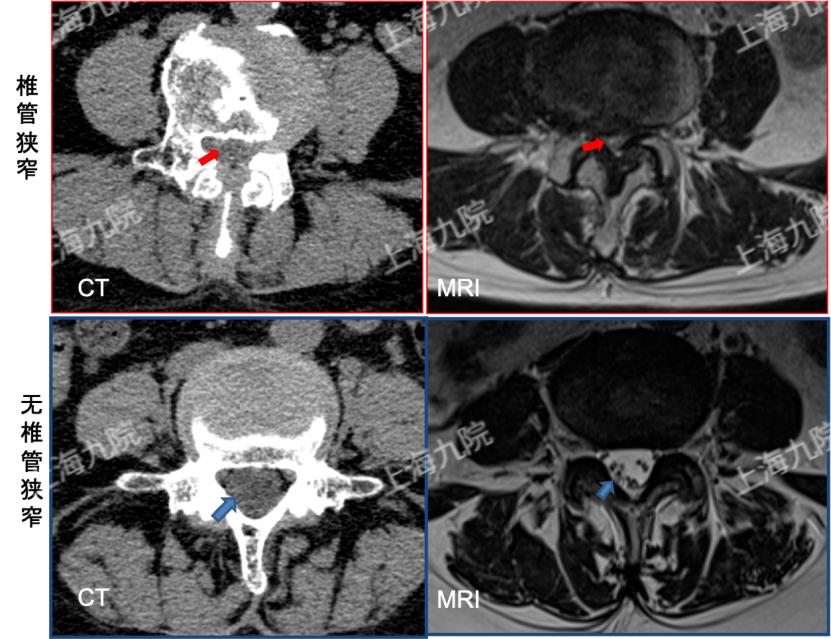

CT扫描:CT有较高的空间分辨力,在横截面上能够清楚地显示骨性和软组织结构,对椎骨、椎间盘、黄韧带的显示可以非常清晰。如果注射显影剂并使用X线生成三维图像,还能显示软组织损伤以及骨骼问题,可以对椎管的狭窄程度进行比较准确的判断。

磁共振成像(MRI):通过电磁波生成脊柱的三维图像,能够显示肿瘤、增生甚至椎间盘和韧带损伤。可以比较清楚地显现出神经根受压的位置和程度。磁共振检查准确率更高,但价格较贵。

正常椎管与椎管狭窄的 CT、MRI影像